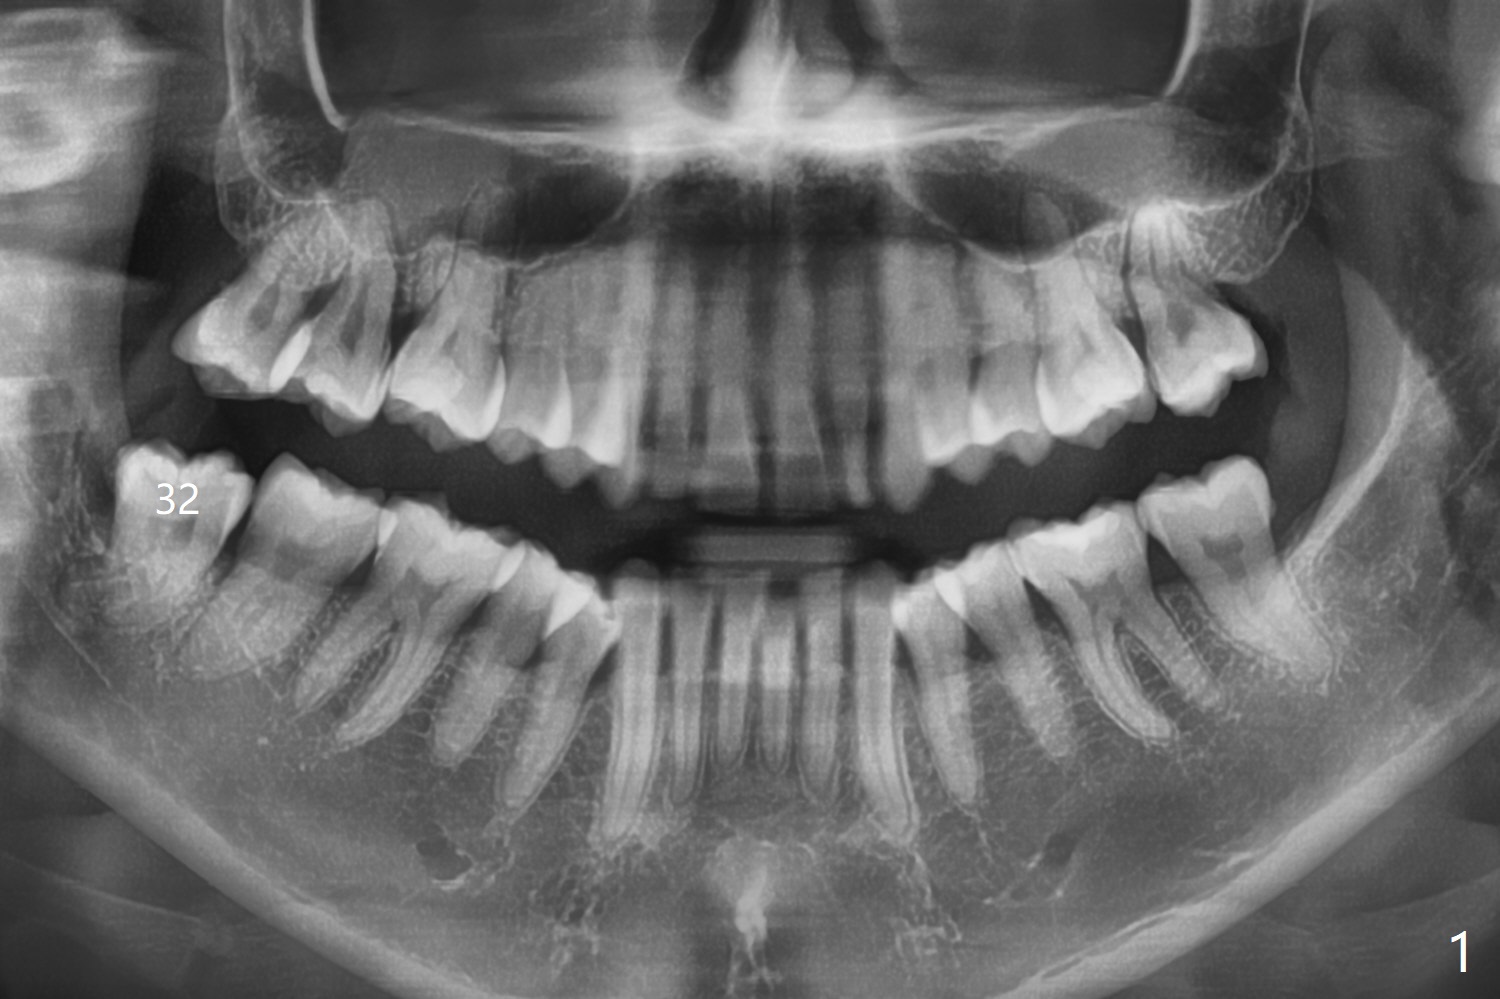

A 37-year-old woman undergoes #1 and 32 extraction (Fig.1). One piece of Osteogen plug is not enough for the #32 socket so that 1 cc of Bond Apatite is added. It would be better to place Bond Apatite first and place Collagen or Osteogen Plug on the top so that the bone cement would be less likelihood to be dissolved by the saliva.